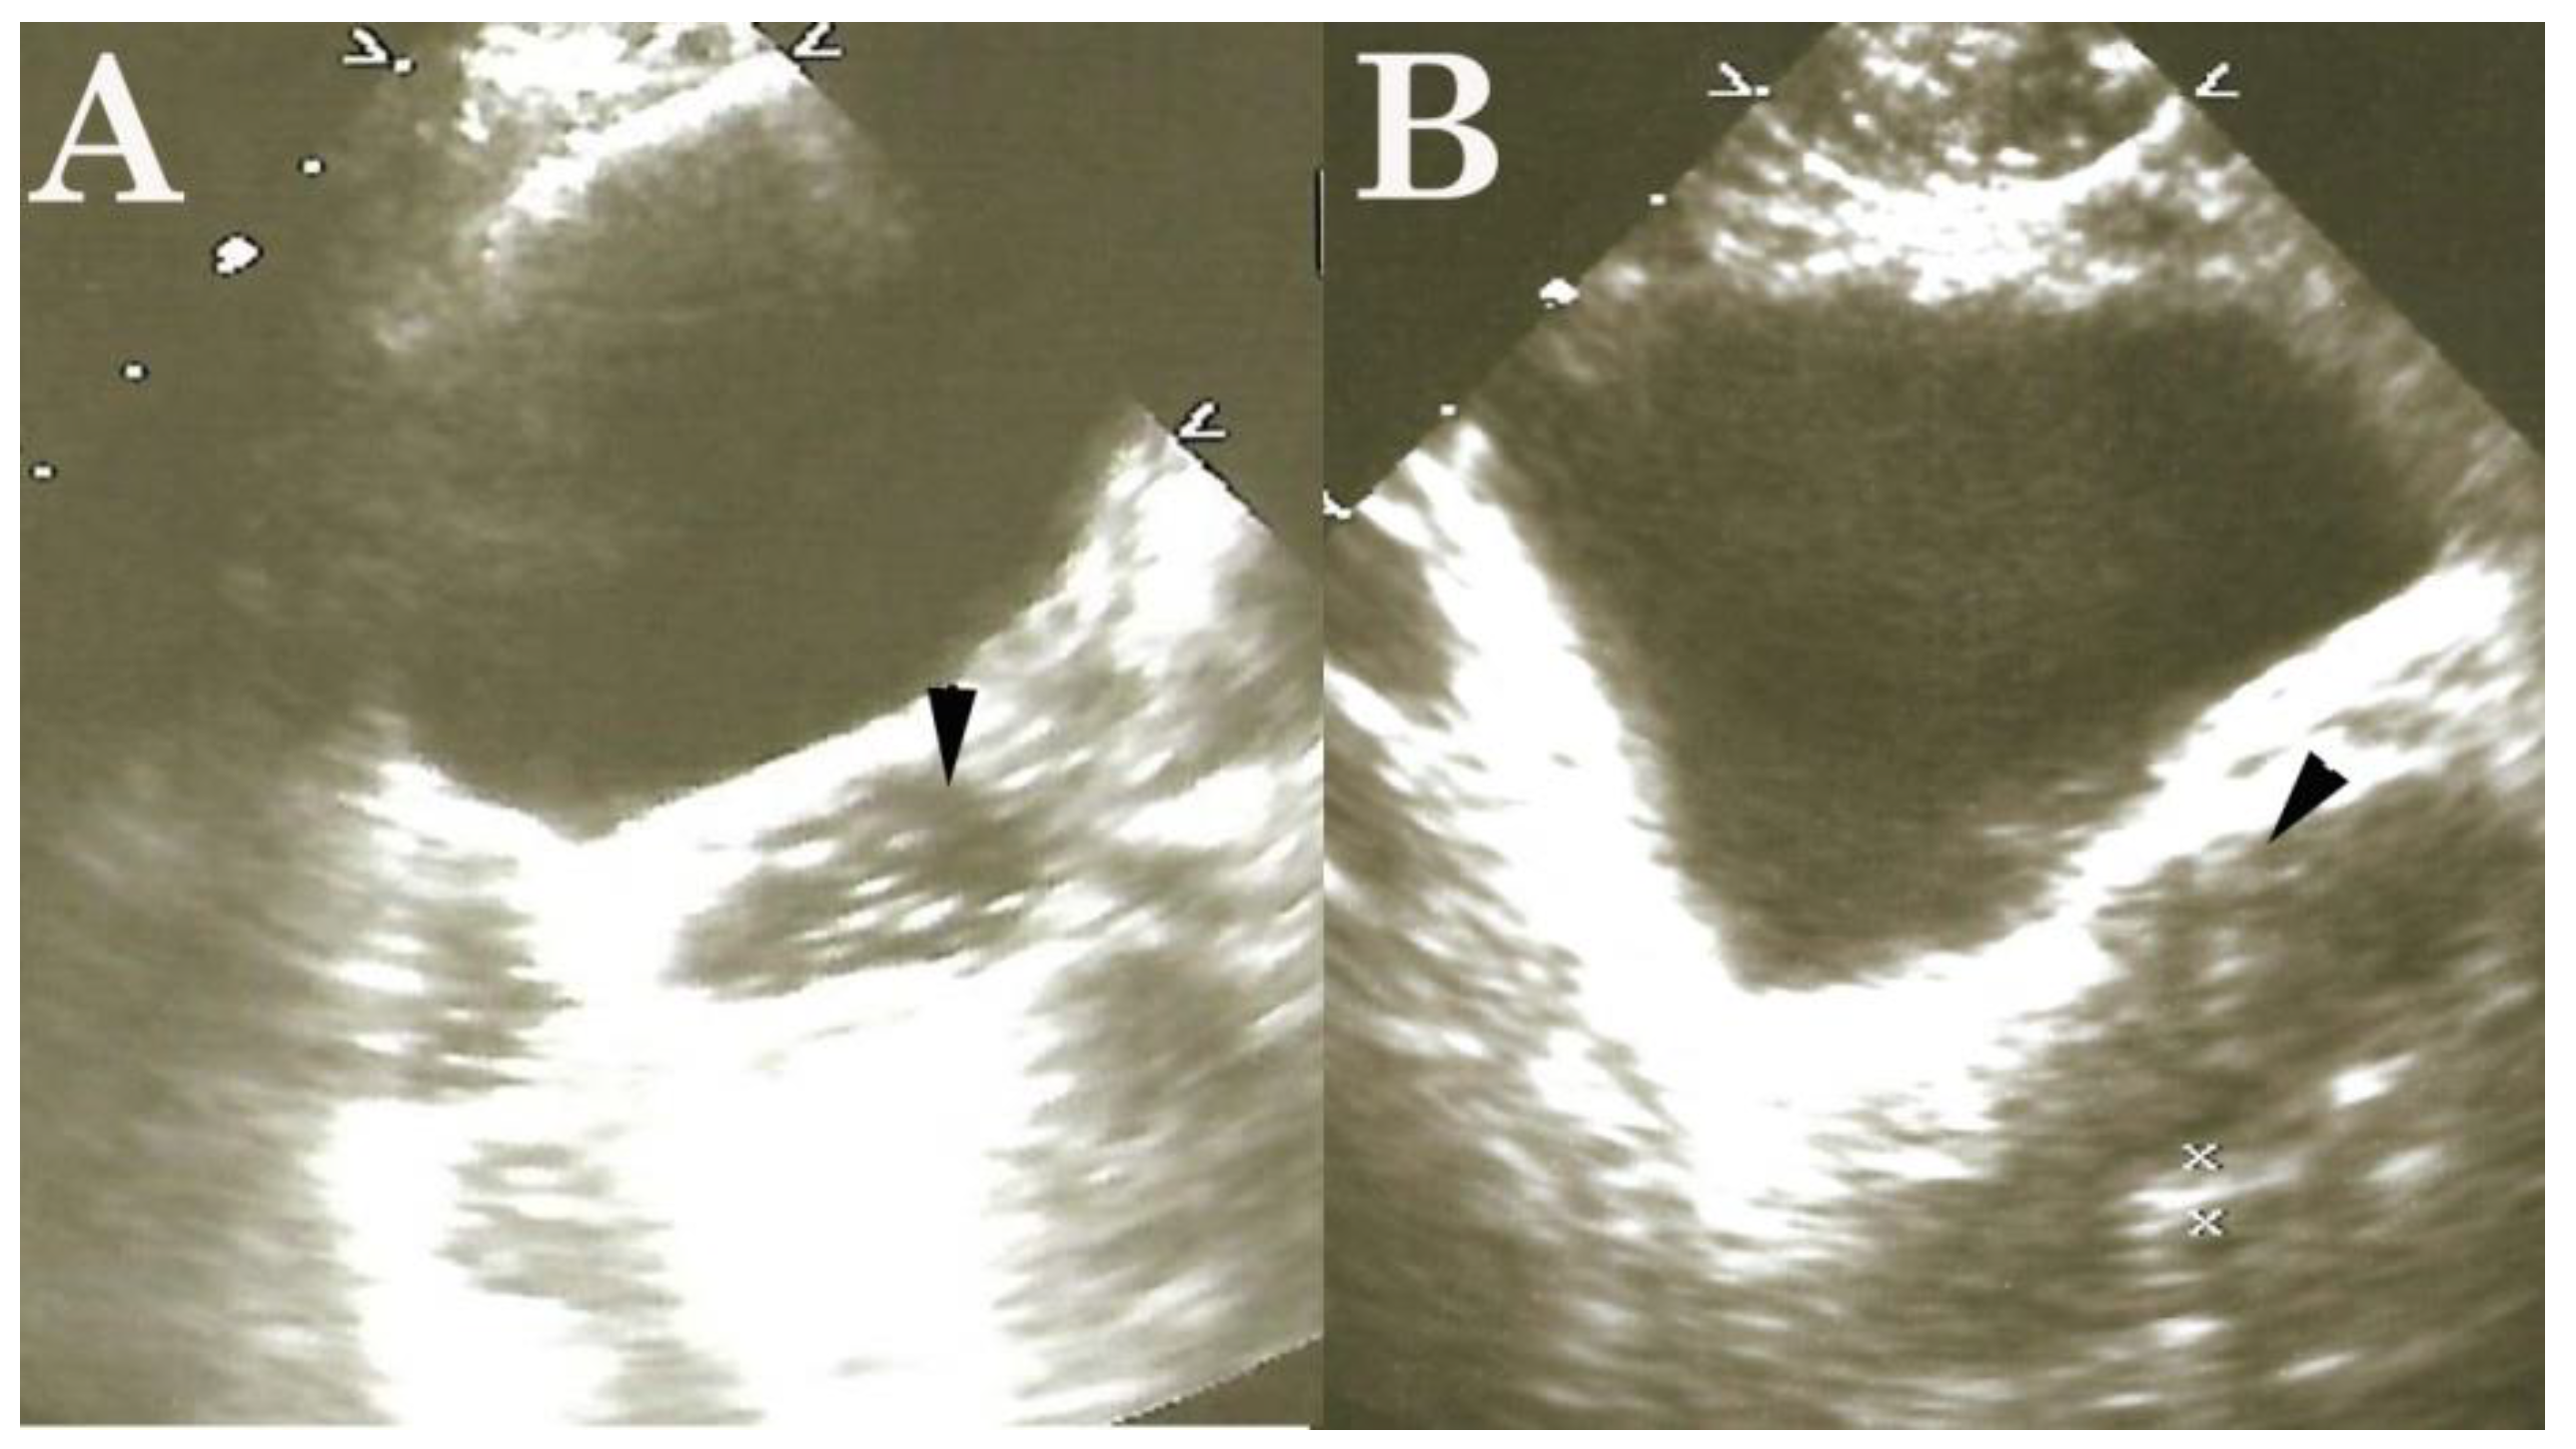

- Njemanze, P.C. , Njemanze J., Skelton A., Akudo A., Akagha O., Chukwu A.A ; et al. High-frequency ultrasound imaging of the duodenum and colon in patients with symptomatic giardiasis in comparison to amebiasis and healthy subjects. J Gastroenterol Hepatol 2008;23:e34-42. [CrossRef]

- Njemanze, P.C. , Njemanze J.T., Ofoegbu C.C., Darlington C.C., Nneke E., Onweni J.A.; et al. High-frequency ultrasound imaging of the intestine in normal subjects and patients with intestinal parasites. In: Ali Abdo Gamie S, Mahmoud Foda E, editors. Essentials of Abdominal Ultrasound. London: IntechOpen; 2019; pp. 91–105. [Google Scholar] [CrossRef]

- Njemanze, P.C. , Njemanze J.T., Ofoegbu C.C., Nneke E., Onweni I.A., Ejiogu U.V.; et al. Technical notes on high-frequency ultrasound duodenography and colonography imaging of giardial lesions. Niger J Gen Pract 2021;19:54-60.